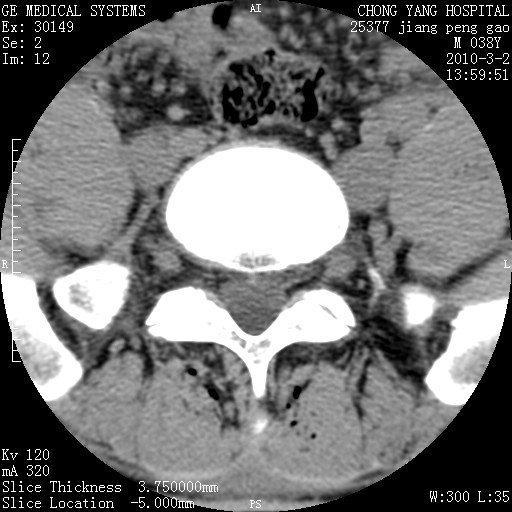

标题: CT24887:M38Y 反复腰痛 无外伤史 未做针灸 竖脊肌为何积气 [打印本页]

标题: CT24887:M38Y 反复腰痛 无外伤史 未做针灸 竖脊肌为何积气

退变,轻度增生/间盘膨出、l5椎后缘软骨结节。

肌间隙积气过多也为退变表现。

椎间盘突出,软组织积气。